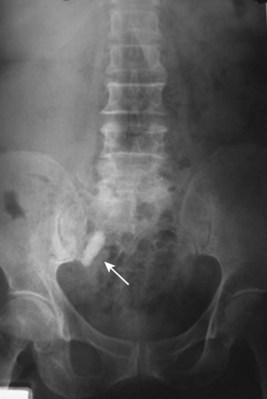

Renal ptosis, although rare, is a real cause of chronic flank or upper abdominal pain. The precise origin of symptoms is unknown, but is likely secondary to either transient ischemia or urinary obstruction (Moss, 1997). It is usually defined as the descent of the kidney by more than two vertebral bodies, but before a definitive diagnosis is made, objective proof that is associated with pain should be obtained. The typical patient with a ptotic kidney is a young, thin female who complains of pain while in an upright position. Supine and erect intravenous pyelography (IVP) can be used for diagnosis, with the finding of interest being descent of the symptomatic kidney by two vertebral bodies (Fig. 55–27). Nuclear imaging may also quantify obstruction of blood flow or drainage in the upright position. Color Doppler sonography in both the supine and upright positions can also be used to evaluate differential blood flow. If a ptotic kidney is present, the expected finding would be diminished blood flow while in the erect position. Before surgical repair, obstruction, decreased blood flow, or significant descent correlating with pain should be documented.

Figure 55–27 Intravenous pyelogram demonstrating bilateral ptotic kidneys in the supine (A) and standing (B) positions.

(From El-Moula MG, Izaki H, Kishimoto T, et al. Laparoscopic nephropexy. J Laparoendosc Adv Surg Tech A 2008;18:230–6.)